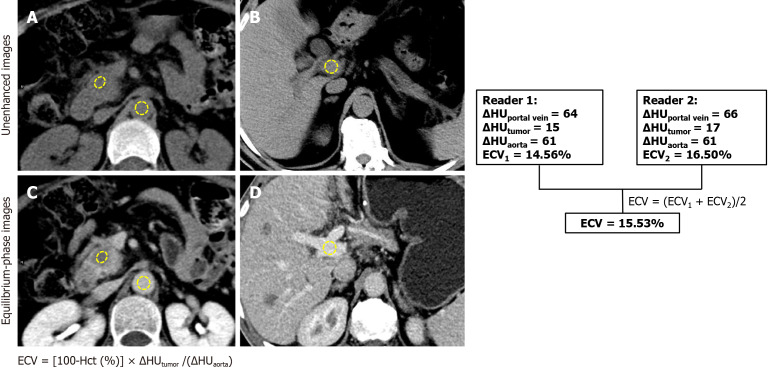

Methods: This retrospective study included 93 PDAC patients undergoing R0 resection and preoperative pancreatic CT from January 2020 to November 2023. Clinical and CT features were analyzed. ECV was calculated using unenhanced and equilibrium-phase CT. Univariable and multivariable Cox regression identified ER predictors, followed by receiver operating characteristic analysis. Recurrence-free survival (RFS) was assessed by the Kaplan-Meier method.